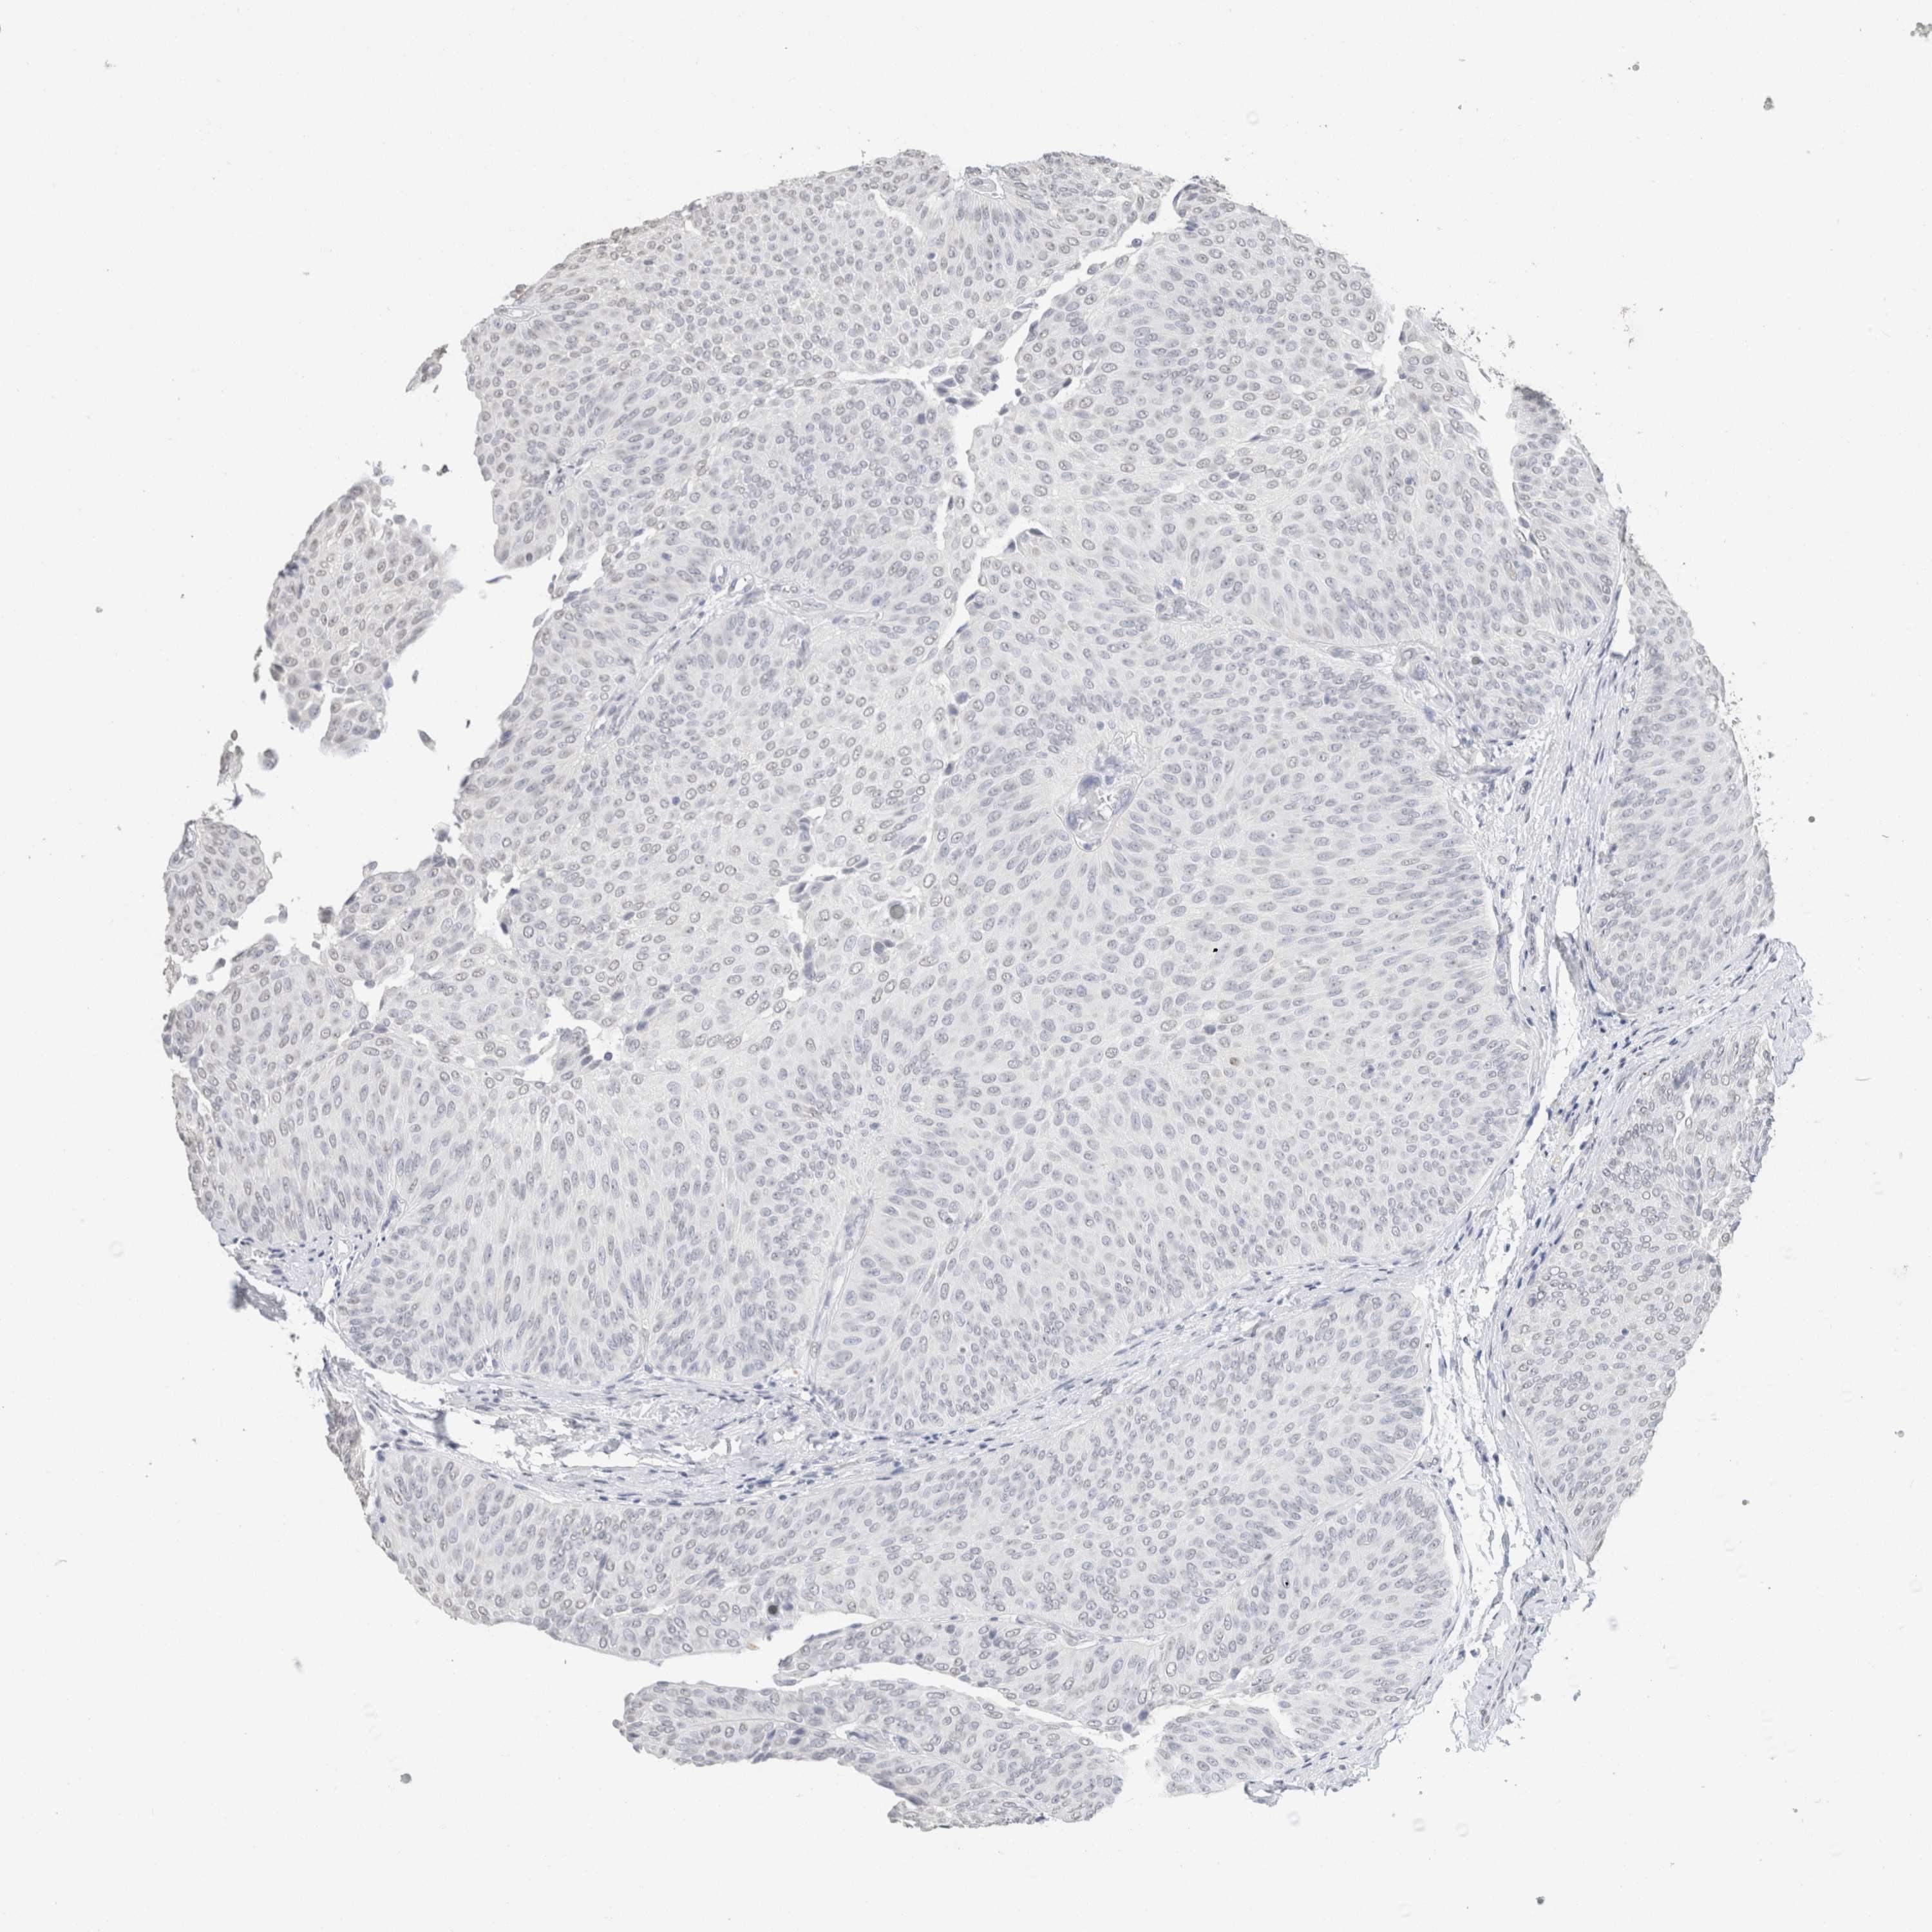

UROTHELIAL CANCER - Protein expressioni

A mouse-over function shows sample information and annotation data. Click on an image to view it in a full screen mode. Samples can be filtered based on level of antibody staining by selecting one or several of the following categories: high, medium, low and not detected. The assay and annotation is described here.

Antibody stainingi

Antibody staining in the annotated cell types in the current human tissue is reported as not detected, low, medium, or high, based on conventional immunohistochemistry profiling in selected tissues. This score is based on the combination of the staining intensity and fraction of stained cells.

Each image is clickable and will lead to virtual microscopy that enables deeper exploration of all samples and also displays staining intensity scores, fraction scores and subcellular localization as well as patient and tissue information for each sample.

Antibody HPA050092

Antibody CAB025368

Urothelial carcinoma, High grade

Urothelial carcinoma, Low grade